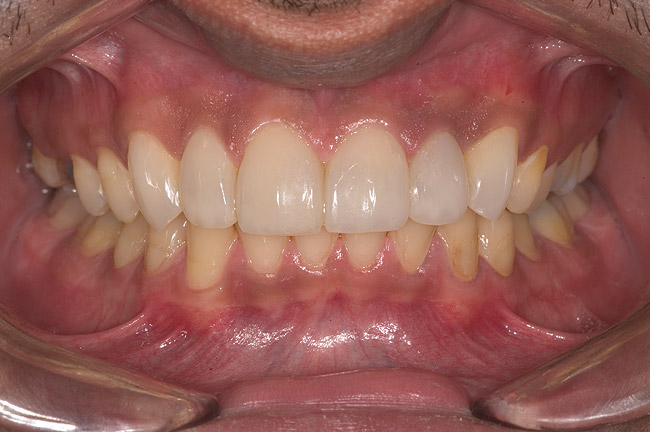

Figure 14  Postoperative smile.

Figure 14

Figure 15  Maximum intercuspation (MIP) after restoration of the lost palatal anatomy.

Figure 15